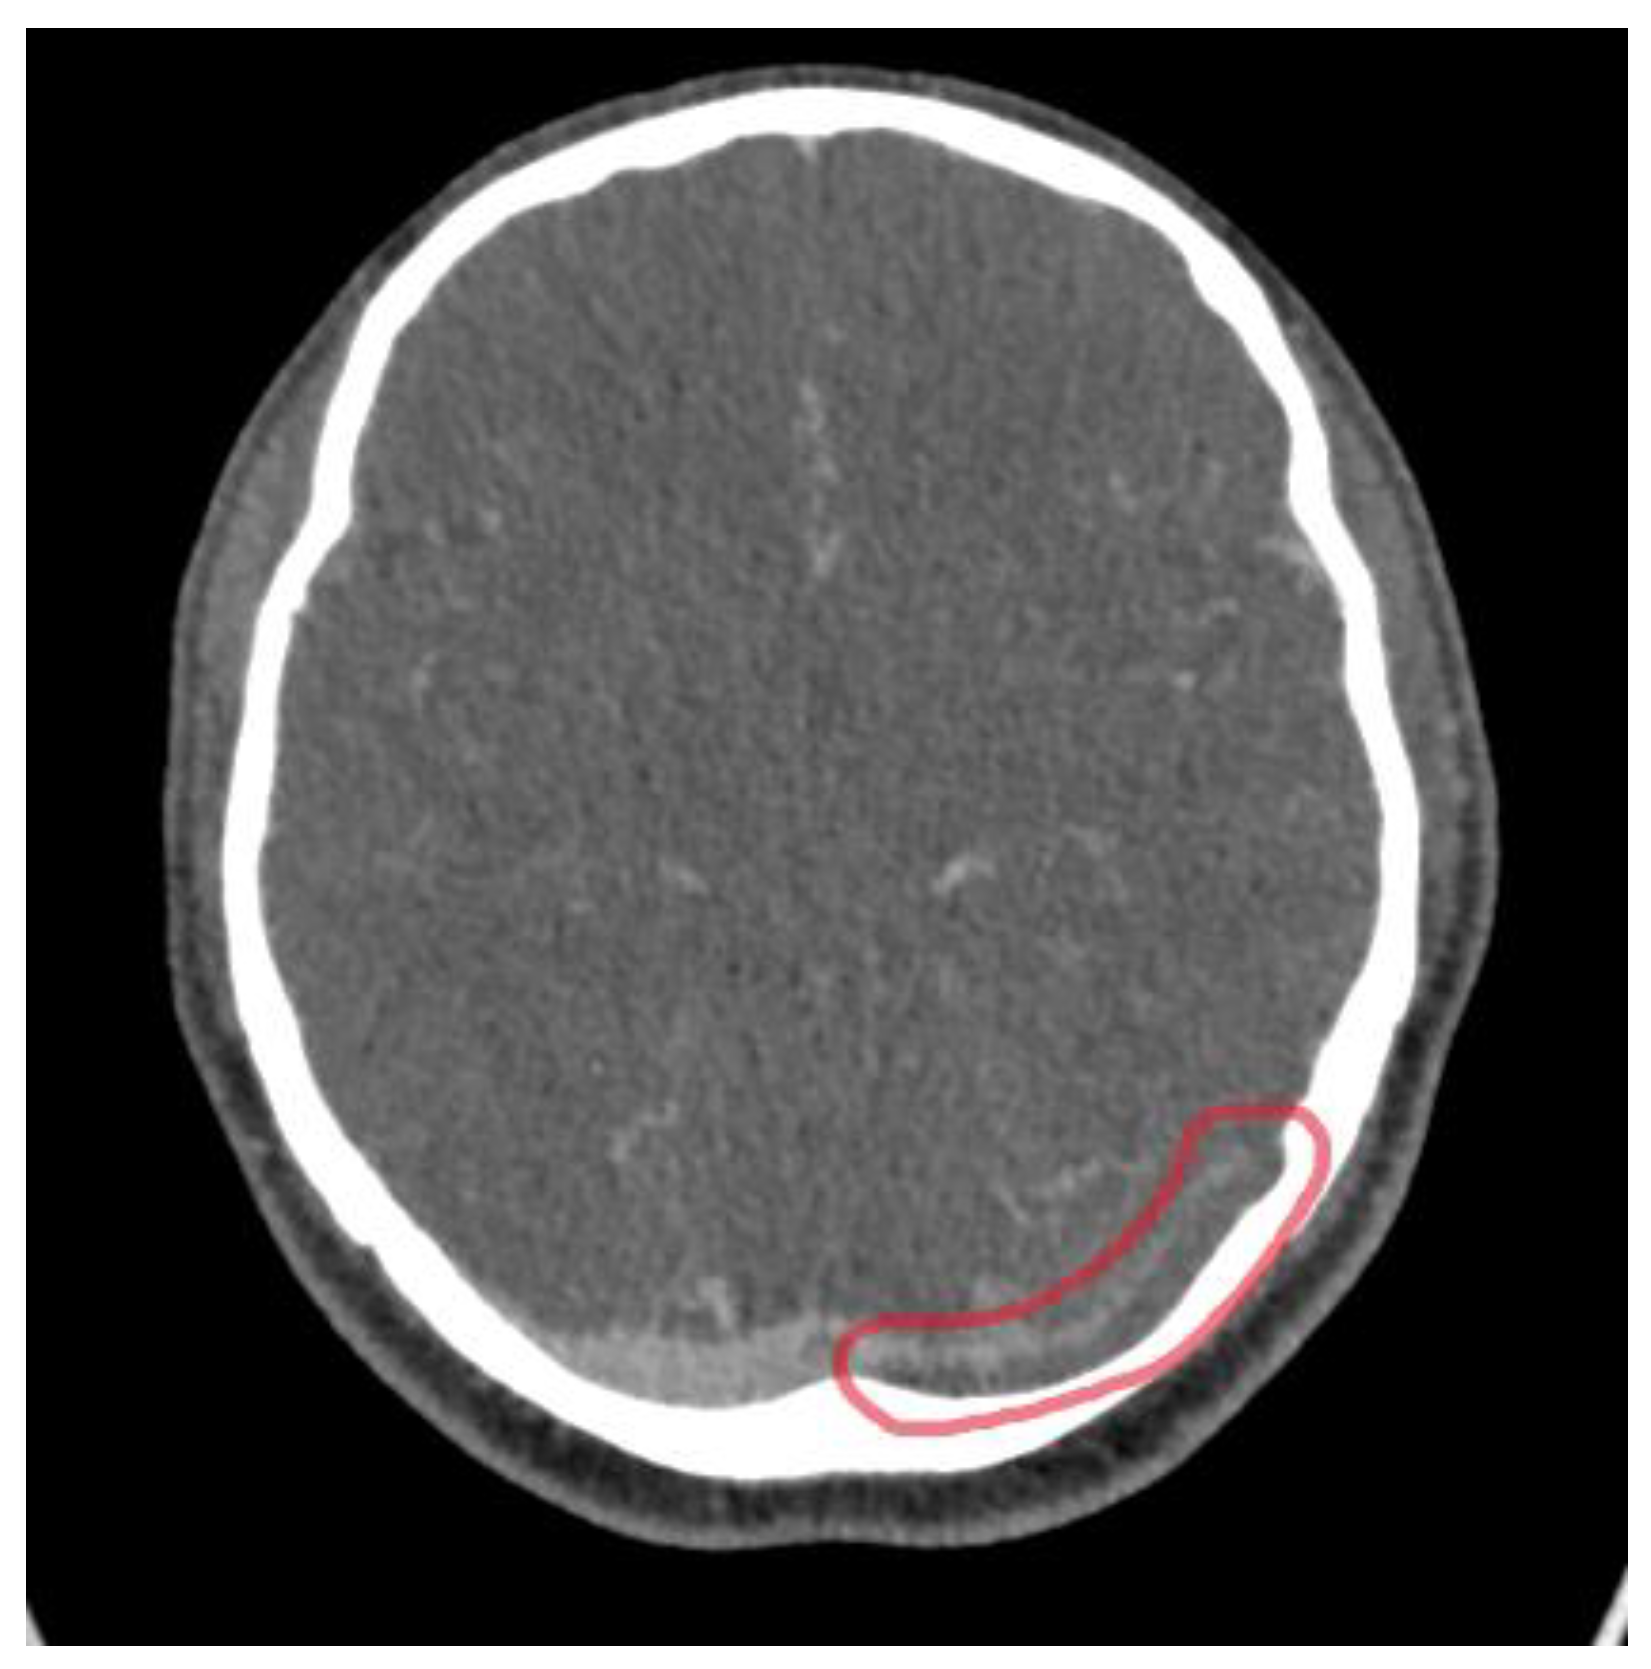

3.2. Imaging Role